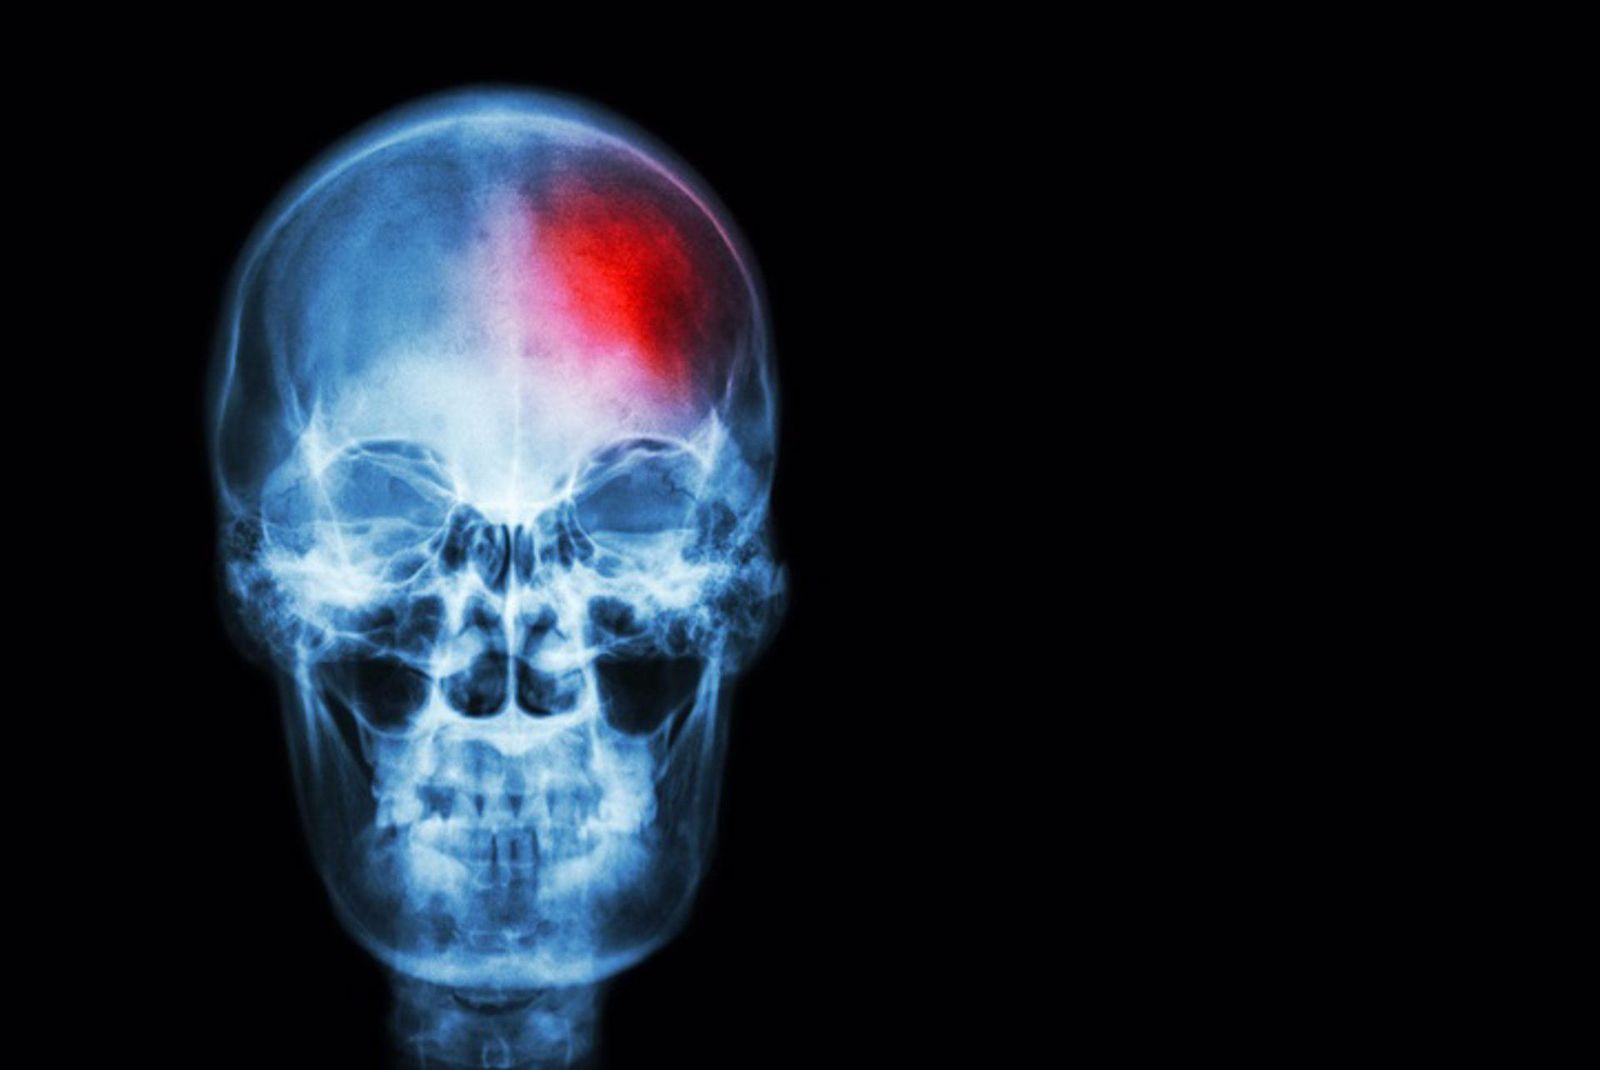

Ictus | EP

El Hospital Clínic de Barcelona ha hecho un hallazgo crucial que puede cambiar la manera decisiva de tratar los ictus y que mantiene la esperanza de las personas que pueden sufrirlo. Así mismo lo demuestra un estudio llevado a cabo por el hospital y publicado en la revista Journal of the American Medical Association (JAMA), publicada por la Asociación Médica Americana de forma semanal desde 1883 y así mismo se detalla en un artículo publicado en el diario AS. Este descubrimiento consiste en una modificación en el momento de suministrar el fámarco usado para tratar el ictus isquémico, lo cual haría que las posibilidades de una recuperación total del paciente tres meses después de sufrirlo sean mayores a un 59%.

Tal y como se detalla en el estudio, el ictus isquémico resulta ser el 85% de todas las embolias y puede ser causado por la obstrucción de un vaso sanguíneo cerebral, lo que provoca un déficit neurológico, tal y como lo ha explicado Arturo Renú en la Cadena SER. A pesar de que no es mortal en todos los casos, puede provocar secuelas permanentes, incluso en aquellos pacientes a los que se les consigue extraer el trombo de sangre.